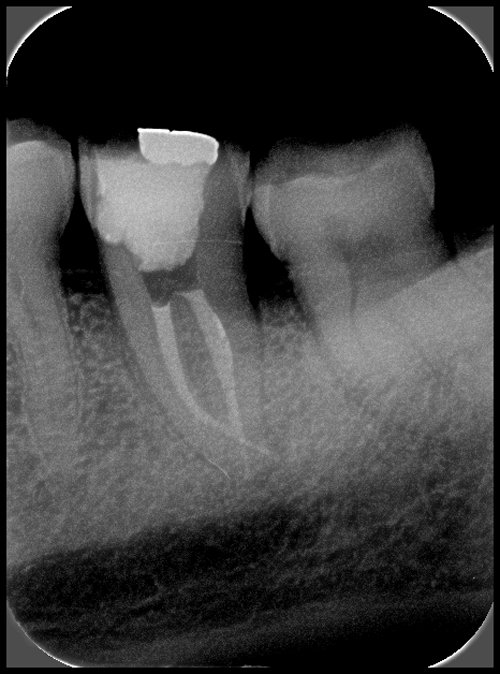

RETRAITEMENT ENDODONTIQUE

Même si la dent a déjà été traitée, elle peut se réinfecter. Plus le traitement est ancien et plus ce risque est important.

Parfois des insuffisances de nettoyage lors du traitement endodontique initial peuvent expliquer pourquoi une dent se réinfecte.

Le traitement endodontique doit être également repris lorsqu’un nouveau projet prothétique est envisagé (réalisation d’une nouvelle couronne ou d’un bridge par exemple). Dans ces situations, il faut reprendre le traitement endodontique.